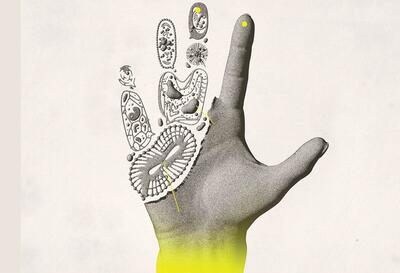

بافت بدن

پروتئین بعد از هضم شدن به واحدهای سازندهی خود یعنی اسید آمینه تجزیه میشود. اسید آمینه به عملکرد و رشد بافتهای بدن کمک کرده و از سلامت عضلات، استخوانها، پوست، مو و ناخن محافظت میکند

فتق نافی چیست؟

رکنا: فتق نافی یک وضعیت شایع است که به بیرون زدگی بافت یا اعضای داخلی بدن از طریق ناحیه ضعیف دیواره شکم اطراف ناف گفته میشود. این مشکل معمولاً در نوزادان و کودکان دیده میشود، اما در بزرگسالان نیز ممکن است رخ دهد و در بسیاری از موارد نیاز به درمان جراحی پیدا میکند.

بیماریهای خودایمنی زمانی ایجاد میشوند که سیستم ایمنی بدن که قرار است با مهاجمان بیرونی مبارزه کند، به اشتباه به بافتهای سالم خود بدن حملهور میشود. این حملات اشتباهی میتوانند التهاب، آسیب و اختلال در عملکرد انواع ارگانها و سیستمها ایجاد کنند.